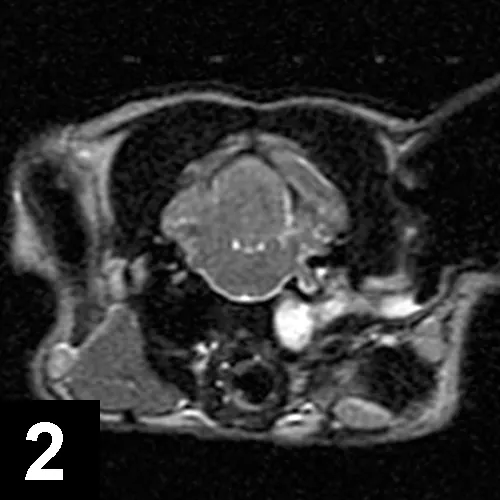

MRI image of the head of a cat with Horner syndrome.

FIGURE 2

Axial T2-weighted MRI of a cat with left-sided Horner syndrome and peripheral vestibular dysfunction secondary to severe otitis.